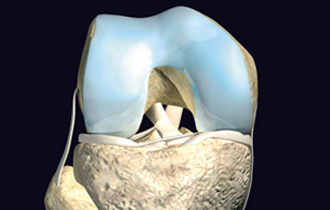

中英合资——关节动力安达(天津)生物科技有限公司是亚太地区首家以研究、生产自体软骨组织细胞移植产品为主的高科技生物企业。具有世界先进水平的自体软骨组织细胞体外培养、移植技术和产品,并拥有自主知识产权,其核心产品包括: CaReS®(软骨再生系统)、CFI(软骨栓)、NuCell(脊椎间盘修复系统)等。公司位于天津港保税区空港物流加工区环河南路,总投资2亿元人民币。

公司拥有的系列产品均采用生命科学领域细胞工程学和工程学的原理与方法,用于软骨相关疾病的治疗,适用于医疗机构骨科临床急、慢性关节软骨缺损疾病的早期修复和治愈性治疗,也可应用于脊椎间盘的软组织损伤细胞修复。是研究和开发用于修复和维护或增进人体各种组织器官损伤后功能和形态的一个边缘性新学科,属于当代前沿科学。

CaReS®(软骨再生系统)等生物组织工程技术和产品的临床应用,将为软骨缺损疾病治疗提供全新的观念并进一步丰富针对软骨缺损疾病的治疗方法,提升骨科临床的治疗水平,与世界接轨并同步发展。通过该技术和产品的临床应用,使广大的患者与欧美国家同步享受高科技生物组织工程技术与产品带来的福祉,提高生活质量,造福于社会。